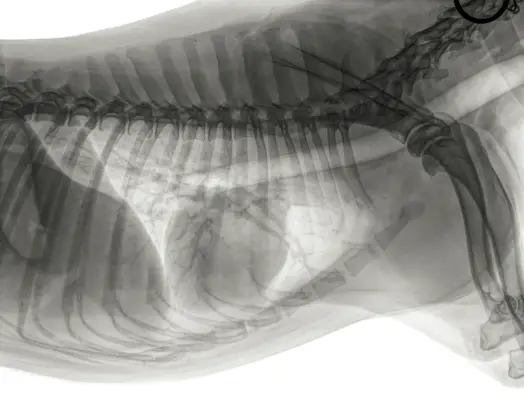

A kutyáknak csak egy szívük van a mellkasukban, és egyetlen szív- és érrendszer részei. Szívük ovális-kúp alakú, a csúcs felé elvékonyodik, és négy kamrából áll: két pitvarból és két kamrából. A két pitvar az a kisebb kamra, amely vért kap a kutya testéből vagy tüdejéből, míg a két nagyobb kamra az oxigénnel teli és oxigénmentesített vért pumpálja a testbe, illetve a tüdejébe.

A kutya szívéhez számos ér kapcsolódik, például artériák és vénák, amelyek a szív- és érrendszer részét képezik, amelyek az egész testben apró erekké, kapillárisokká ágaznak.

A kutya szíve minden összehúzódáskor vért és oxigént pumpál a szervezetbe. A kutya szívének jobb oldala oxigéntelenített vért pumpál a kutya tüdejébe oxigénellátás céljából. Az oxigéndús vért a bal oldal fogadja, majd az oxigéndús vért átpumpálják az aortán, és eljuttatják a kutya többi részéhez. Ezt az oxigéndús vért a kutya szöveteibe és szerveibe juttatják, hogy fenntartsák azok működését.

A kutyáknak egy szívük és egy szív- és érrendszerük van. Szívük a mellkasuk közepén helyezkedik el a tüdejük között, kissé balra. A szív feladata, hogy vért pumpáljon az egész testben, és oxigénmentesített vért kapjon, amelyet a tüdőbe pumpálva oxigénnel lát el.